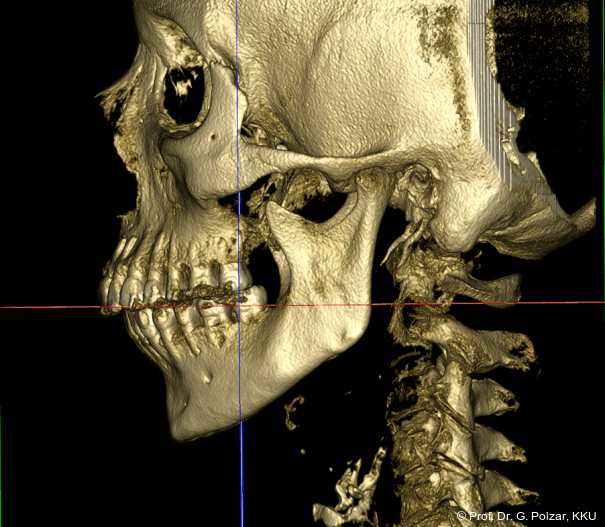

KG-Position: Die 3D-Ansicht im DVT zeigt eine vorverlagerte UK-Position bei neutraler Okklusion (Abb. 4a+b).

Beide Kiefergelenke (KG) befinden sich nun in zentraler Kondylen-/Fossa-Position bei neu­traler Okklusion (Abb. 10+11).

Nach der Umstellungsosteotomie mit der UK-­Vorverlagerung kann die Patientin besser zubeißen. Bei maximaler Interkuspidation in neutraler Okklusion befinden sich nun beide Kiefergelenke in zentraler Po­sition zur Gelenkpfanne. Der geringe Abstand des Caput mandibulae zur Schädelgrube lässt auf eine Diskusverlagerung schließen (Abb. 20a+b).